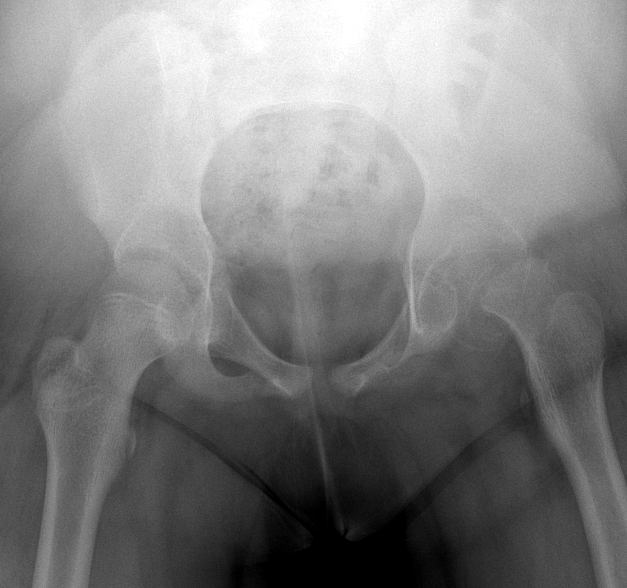

What’s the Diagnosis? Gepost op 26 september 201926 september 2019 door netwerkvsseh What’s the Diagnosis? By Dr. Loran Hatch @emdaily.cooperhealth.org Dit delen: Delen op X (Opent in een nieuw venster) X Share op Facebook (Opent in een nieuw venster) Facebook Delen op LinkedIn (Opent in een nieuw venster) LinkedIn E-mail een link naar een vriend (Opent in een nieuw venster) E-mail Afdrukken (Opent in een nieuw venster) Print Vind-ik-leuk Aan het laden... Gerelateerd